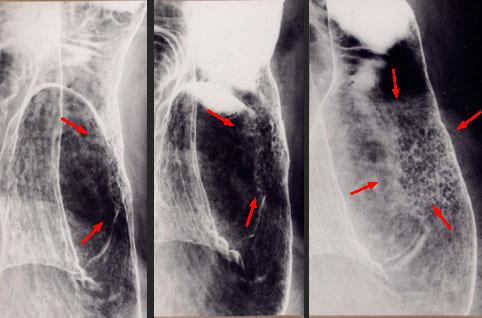

표면함몰형(IIc형) 조기위암과 유사한 형태를 보인 위 유전분증

염증성・궤양성 질환/소화관 유전분증

위(부위)/전정

X-P